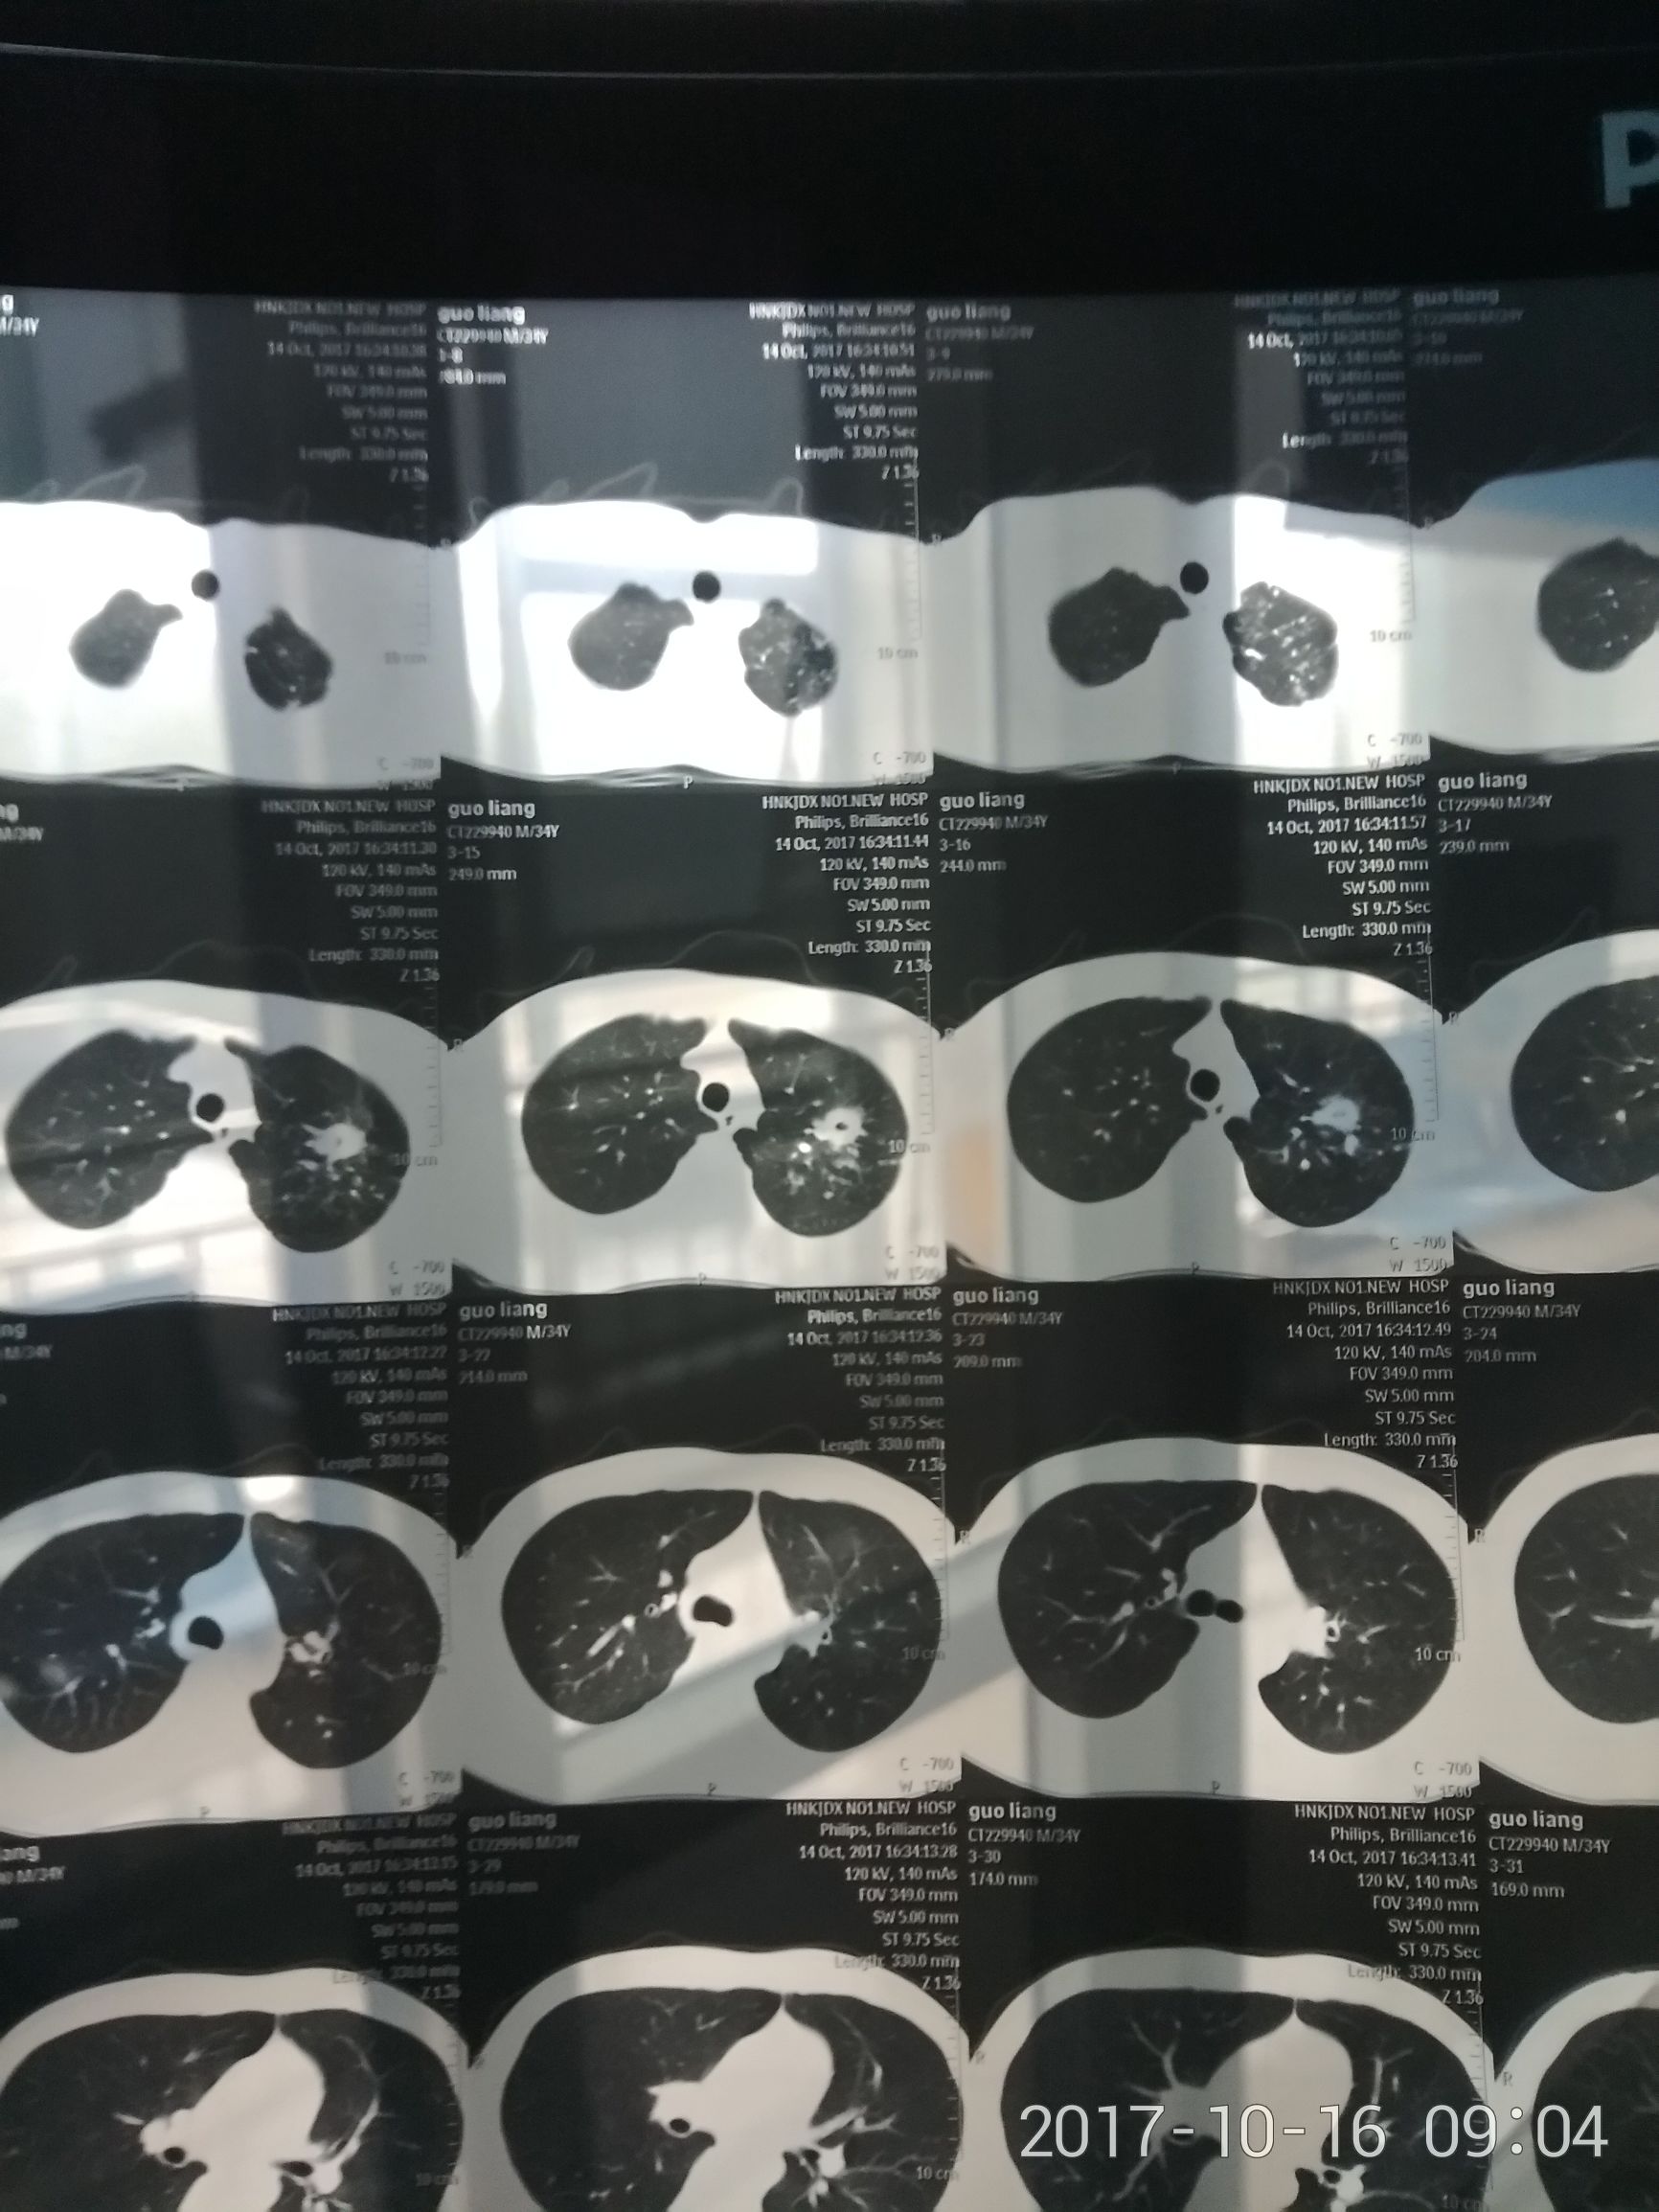

抗核日记:一个肺结核患者的治疗过程㈠ ​ct可以看到图上也是右边是左肺,清楚的看到右肺没问题,左肺一块病灶,并且中间有一个小洞,说明我这个已经有段时间了,可自己一点感觉都没有。。。可想这个病藏的多深。。。

抗核日记:一个肺结核患者的治疗过程㈠ ​部分病灶钙化,说明我之前就得过一次,可是自己好了,也是一点都不知道。。。